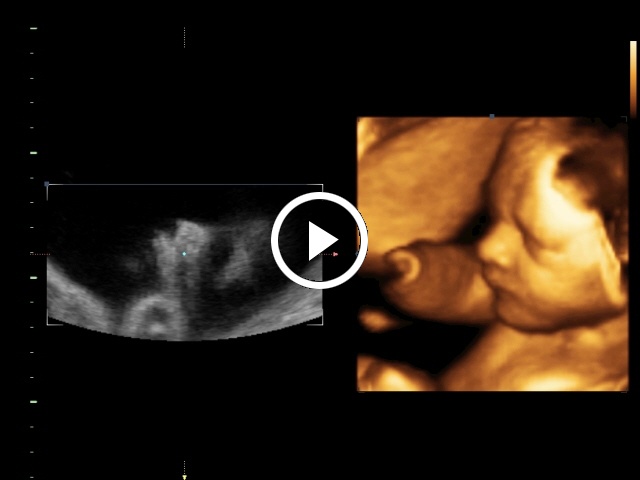

Példák a Cine memória tartalmának visszajátszására:

3. 4D-mód Cine képei